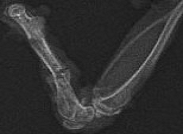

На рис. 6, 7, 9, 11 представлены типичные рентгенограммы бедренной кости крыс через 30 сут. после остеотомии, общего равномерного гамма-облучения 3,0 Гр и воздействия низкочастотными акустическими колебаниями разного диапазона. На рис. 13, 15 представлены рентгенограммы бедренной кости крысы через 30 и 45 сут., соответственно, после остеотомии, общего равномерного гамма - облучения 3,0 Гр, без стимуляции остеорепарации низкочастотными акустическими колебаниями.

Группа 1

Рентгенологически на 30 сут. эксперимента определяется относительно массивная периостальная фиброзная мозоль с выраженной резорбцией отломков кости. В трех случаях прослеживается кортикальный слой в области остеотомии с частичным восстановлением костномозговой полости (рис.6).

Рис.6. Типичная рентгенограмма бедренной кости крысы группы 1 через 30 сут. после остеотомии и общего равномерного гамма - облучения 3,0 Гр. Воздействие НАК - частота 5 Гц.

Оптическая плотность зоны регенерата-0,358 ± 0,024, р < 0,05.